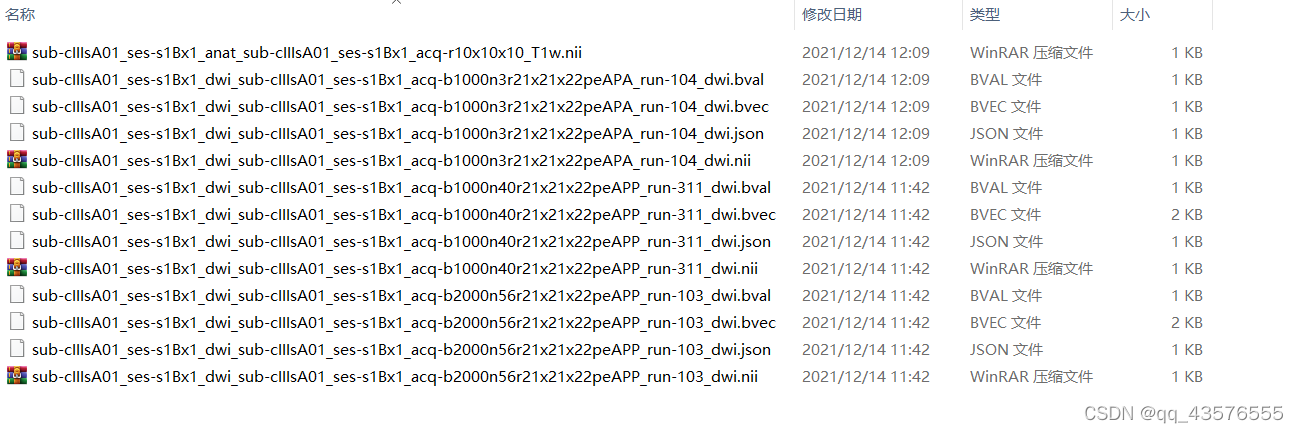

数据来源openneuro,这里我们下载了三组弥散项数据以及一组结构项数据,包括第一个被试sub-cIIIA01的第一个session ses-s1Bx1的T1w像,和dwi下面的run103/104/311的所有文件,包括:.nii.gz/.bval/.bvec/.json

b值为弥散梯度,b值的增加,弥散权重会增加,会提升不同组织之间的对比度,但会影响图像的信噪比,目前倾向于收集多个b值的数据进行综合分析。我们先简单看一下这些数据的信息。